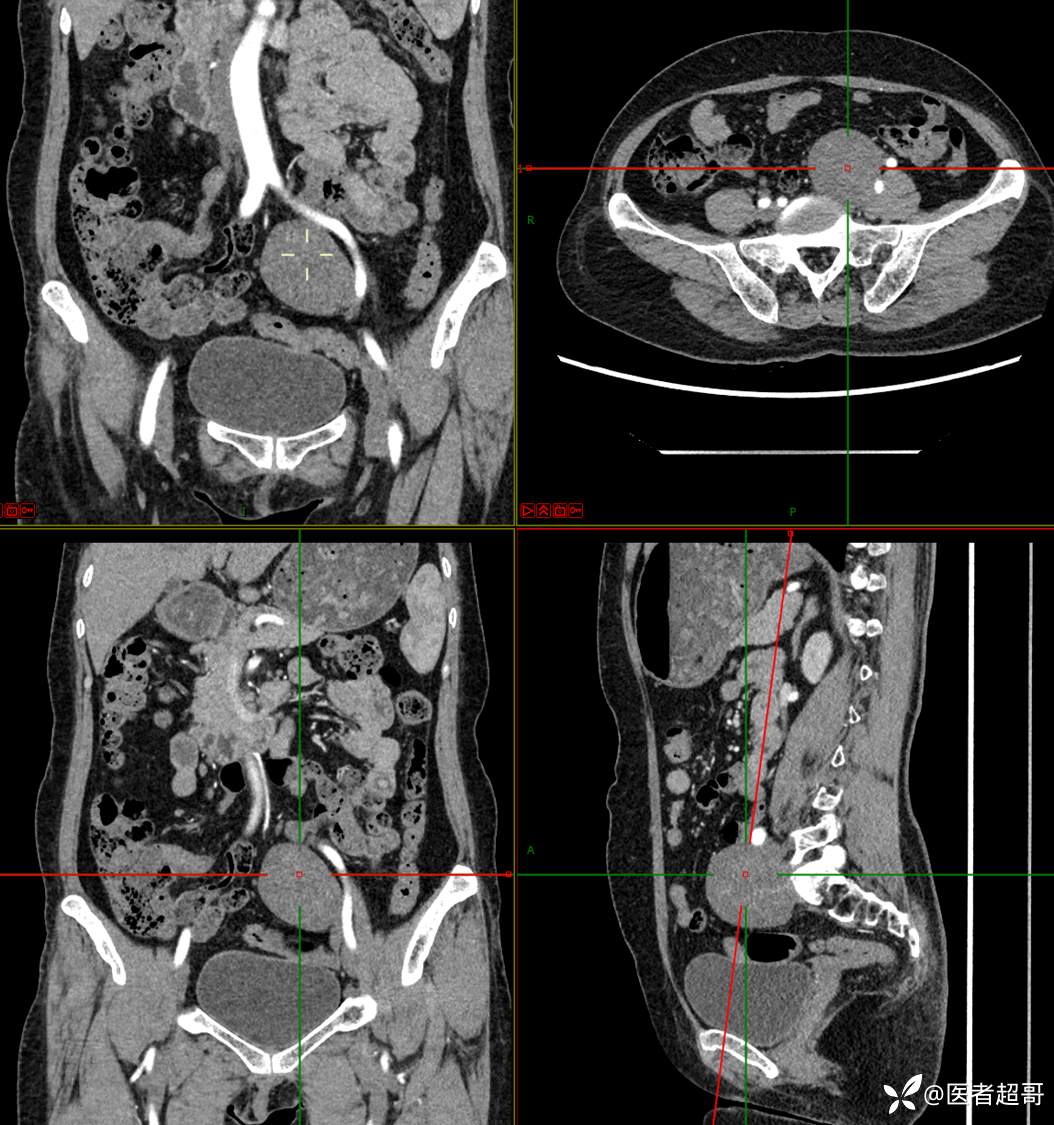

【影诊笔记559】查体发现右输尿管结石1周,发现腹膜后肿物,请分析,有病理!

•主 诉:查体发现右输尿管结石1周。

•现病史:患者1周前因小便不适来我院门诊行彩超检查提示右输尿管结石并右肾积水,伴腰疼,无血尿,无寒战,高热,患者求其进一步诊治,门诊以“右输尿管结石并右肾积水”收入院,患者自发病以来,神志清,精神可,饮食睡眠可,大便便秘,近期体重无明显增减。